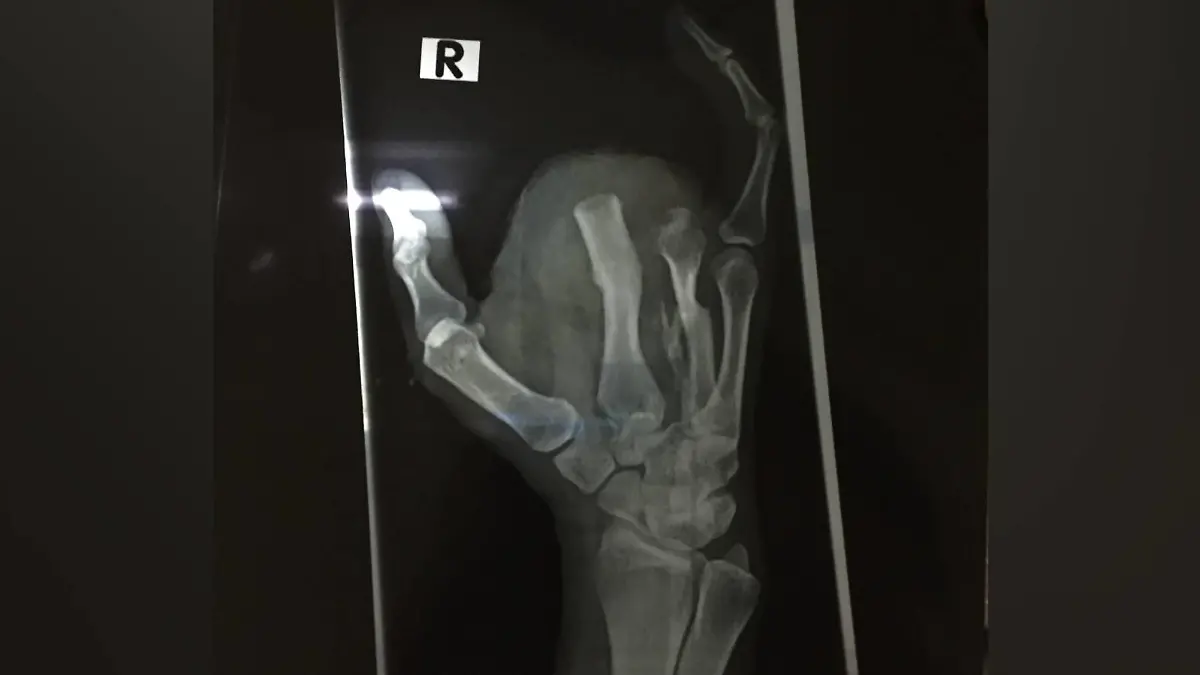

Doch was genau ist eigentlich das Proteus-Syndrom? Vor 33 Jahren wird Yasemin Seber damit und dem Clove-Syndrom geboren. Beide Syndrome sind sehr selten. Seber erzählt, dass sie ein großes Feuermal auf der Brust hat und riesengroße Finger hatte, die ihr zum größten Teil bereits amputiert wurden: „Ich wurde mit zehn Fingern geboren. Fünf davon waren jedoch extremst deformiert und einfach zu groß. Zudem hatte ich einen großen Tumor im Herzbeutel und an der Schlagader, die über einen Kilogramm schwer waren. Sie wurden sofort entfernt, da ich sonst als Baby nicht überlebt hätte“, erklärt die Selbstständige, die ihren eigenen Online-Shop betreibt.

Auch wenn eine Amputation alles andere als einfach ist: Für Yasemin Seber ist es ein Befreiungsschlag, als ihr nach und nach ihre Finger abgenommen werden, „weil alles Sichtbare vom Proteus-Syndrom plötzlich weg war. Meine Finger haben so geschmerzt und waren so riesig. Ich saß regelmäßig auf dem Boden und habe vor Schmerzen geschrien.“ Plötzlich, so erzählt sie, habe sie sich nicht mehr wie ein „kleines Monster“ gefühlt, sondern wie eine Frau.